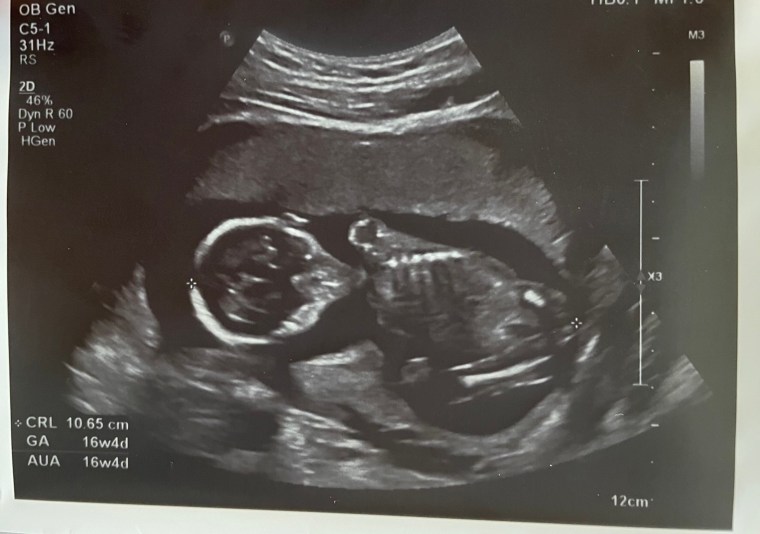

• 第十六周 & 性別揭曉派對